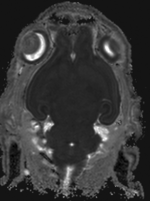

Surface model of original unregistered brains original, not registered

original unregistered brains original, not registered